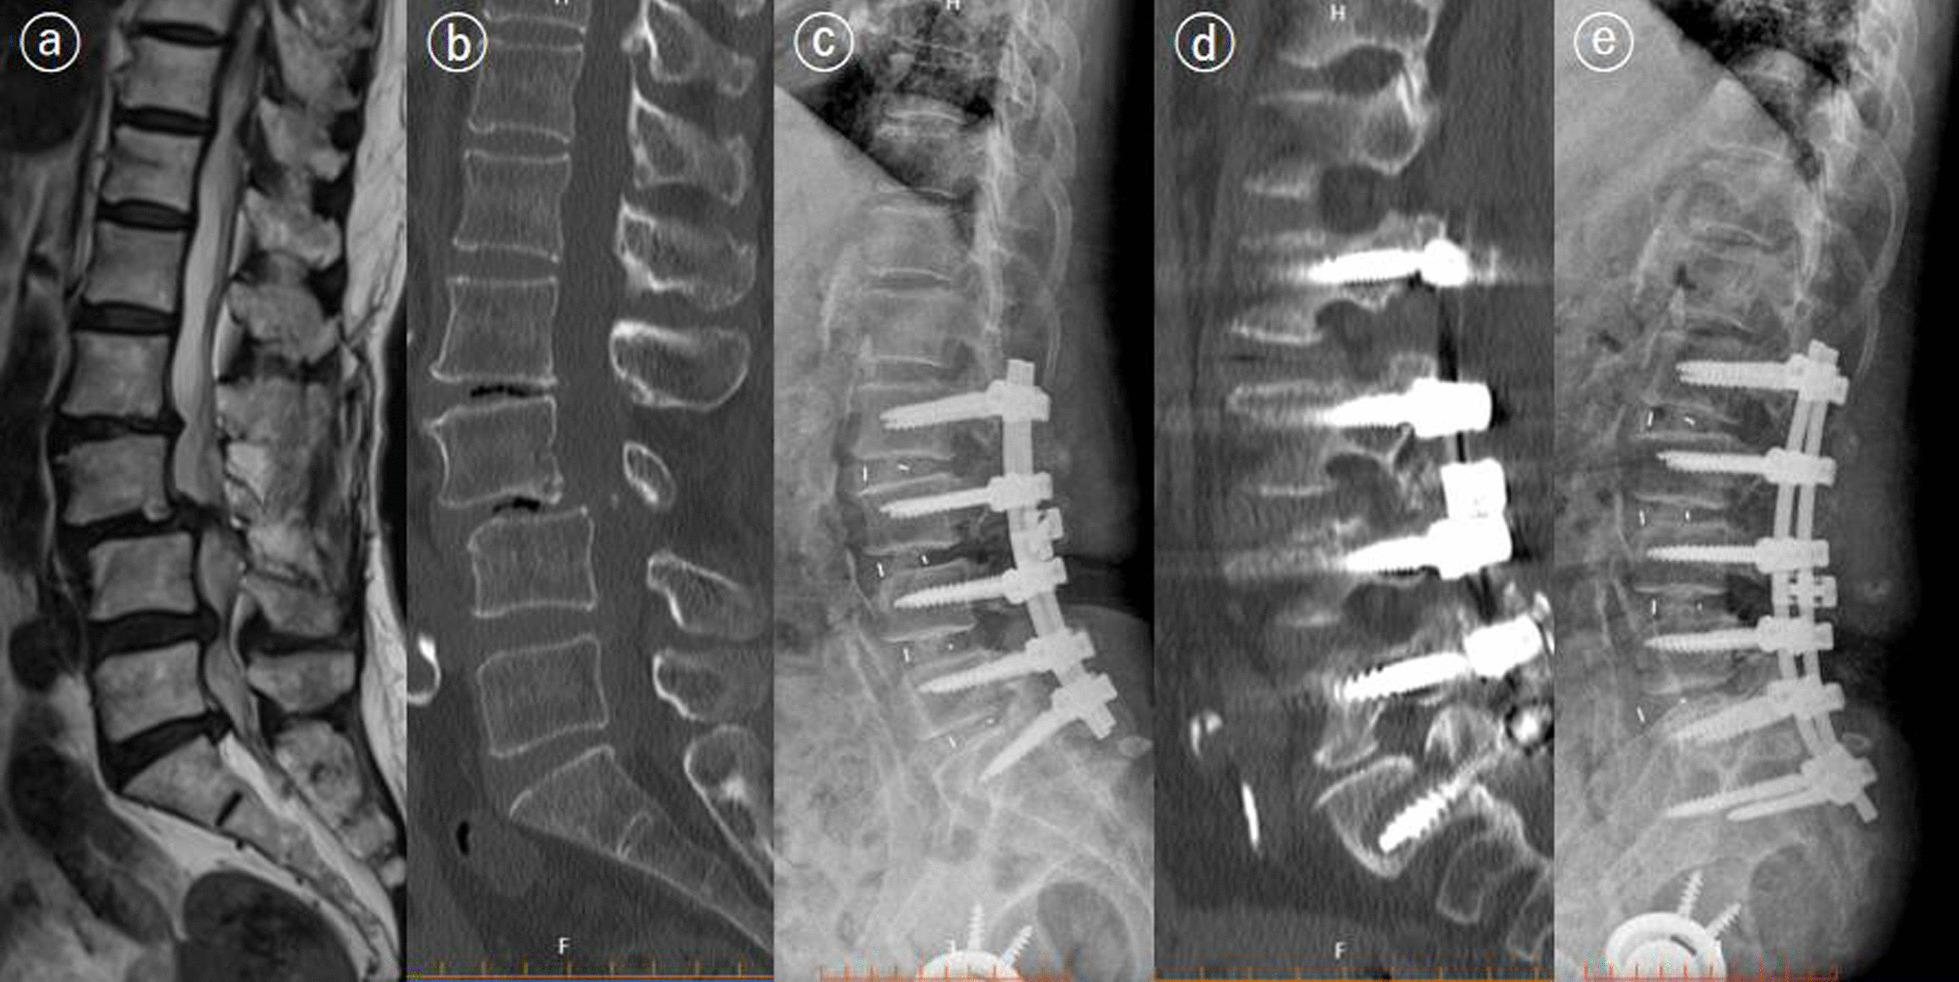

Fig. 3.

A 74-year-old patient underwent second surgery for screw misplacement. The patient underwent posterior decompression and fusion surgery for L3–L4 grade 2 spondylolisthesis and stenosis (L4–L5, L5–S1) (a, b). The postoperative X-ray was normal (c). The patient had moderate pain, and CT revealed bone union and screw displacement at the 1-year follow-up (d). The patient underwent revision surgery and achieved adequate pain control (e)